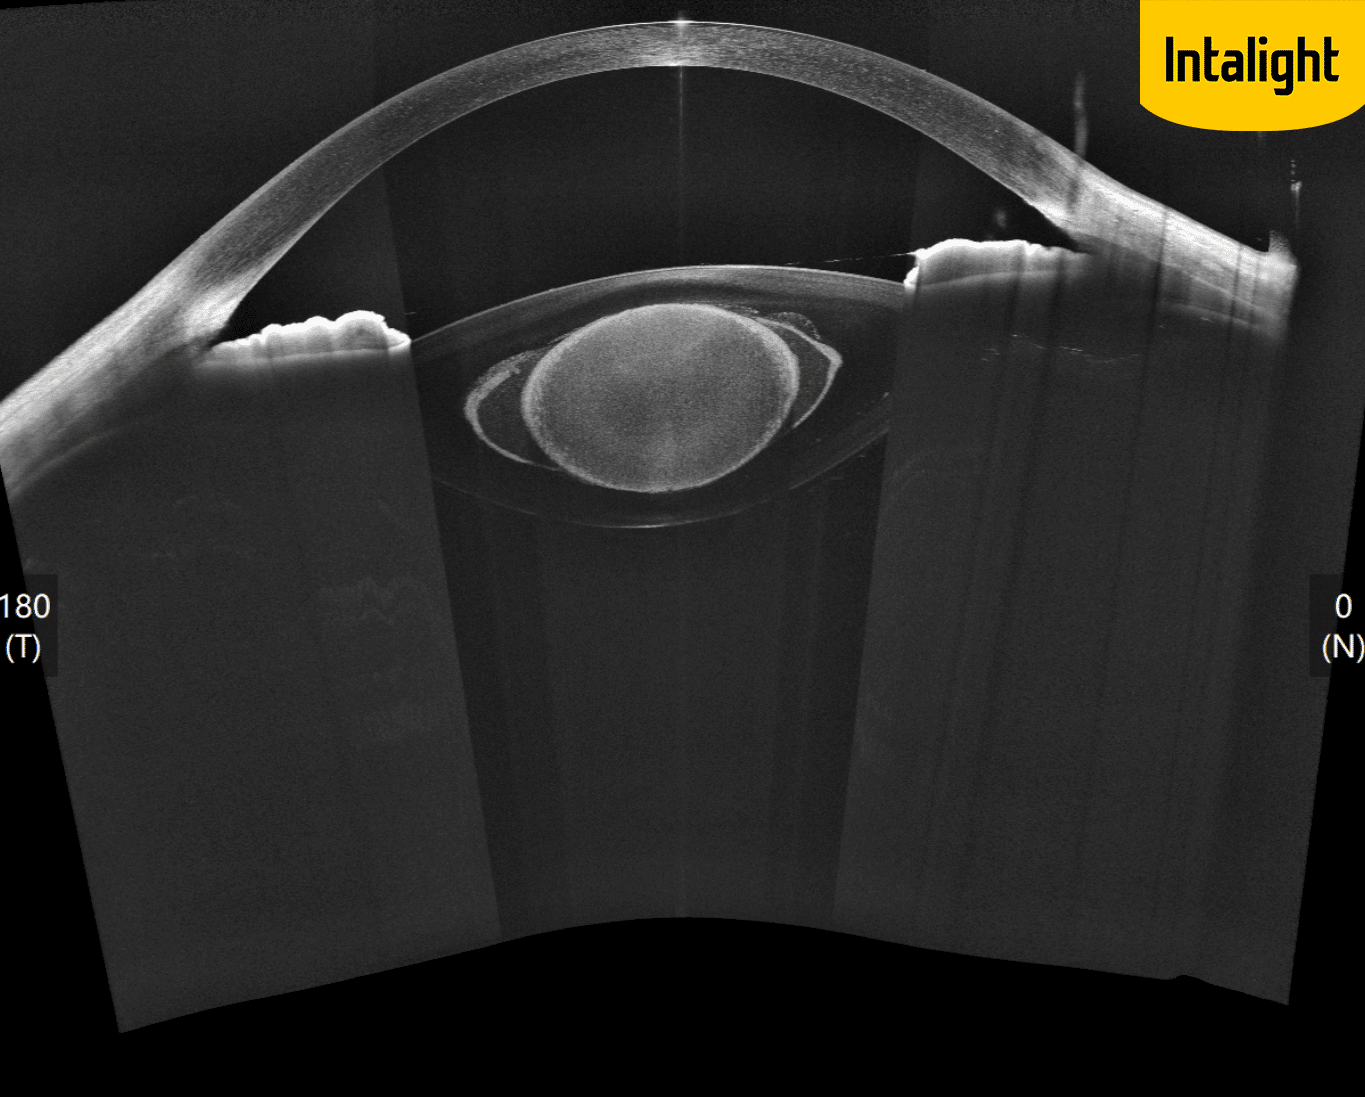

DREAM OCT : analyse grande profondeur du segment antérieur